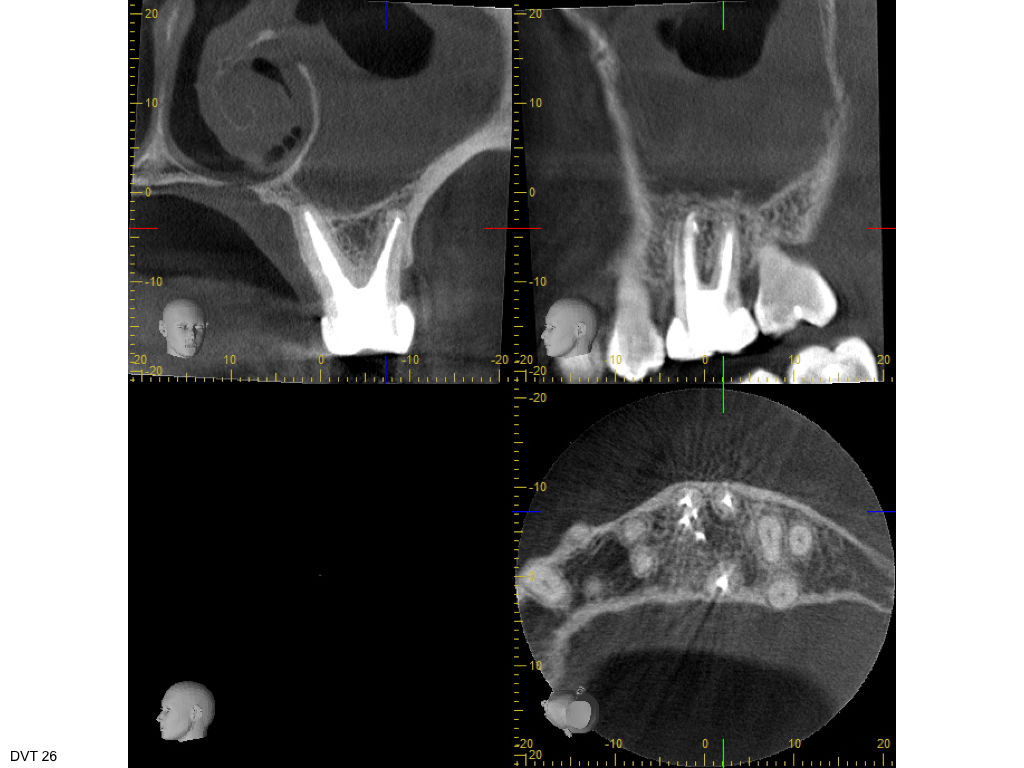

Heilung oder was?